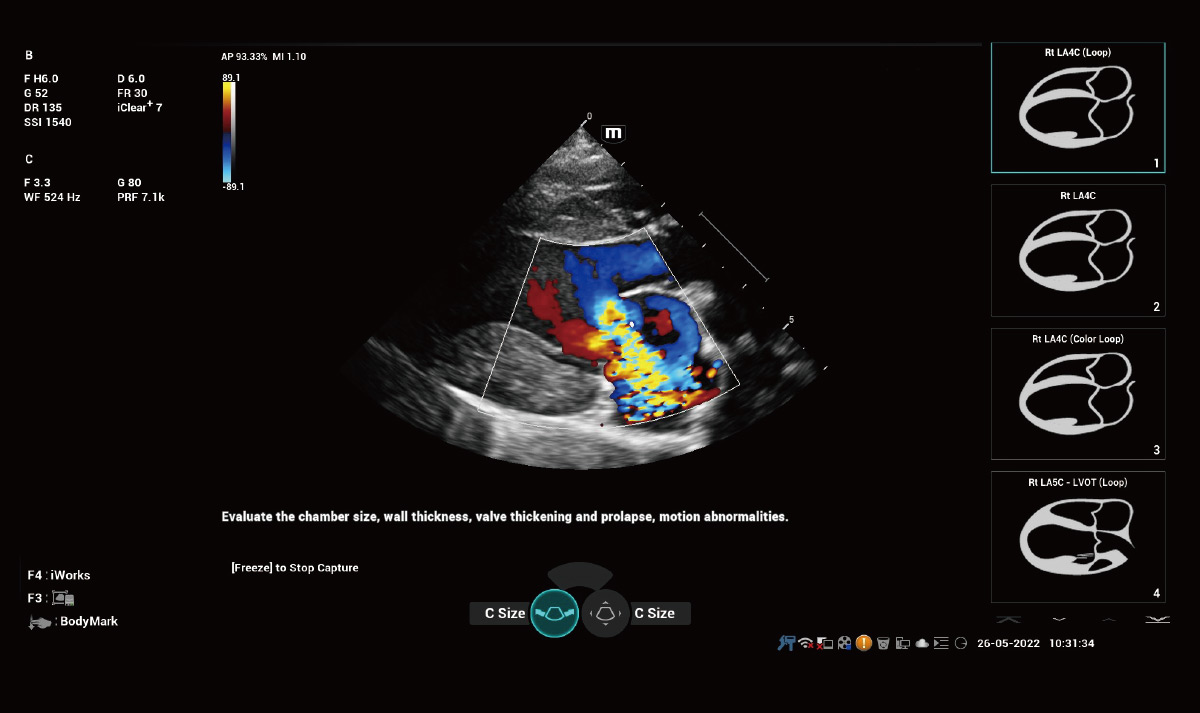

Solución de cardiología

Análisis cuantitativo del movimiento y sincronización del miocardio – TDI QA

TDI QA con un máximo de 8 ROI permite análisis simultáneos de 8 regiones del miocardio, incluida la velocidad del movimiento del miocardio, la tensión del miocardio, la tasa de tensión y la sincronía del miocardio.